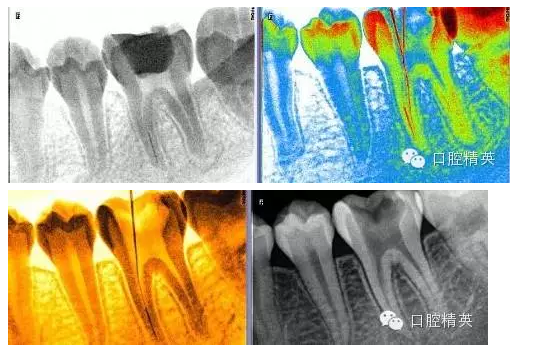

1,術(shù)前X-ray,常規(guī)術(shù)前攝片,

3,術(shù)前左下6近中根管斷針X-P,斷針長(zhǎng)度約4MM,根尖慢性炎癥影像。。。

9,斷針取出術(shù)后X-P,RCT待續(xù)。。。